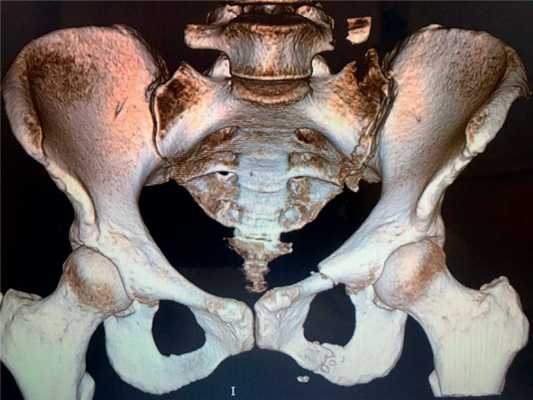

По первичным обзорным снимкам таза диагностировали нестабильность тазового кольца в горизонтальной и вертикальной плоскости. На переднезадней рентгенограмме лучше всего выявлялись повреждения переднего полукольца таза: разрывы лобкового симфиза, переломы лобковых и седалищных костей. Уточнение диагноза проводилось после выхода пострадавших из тяжелого состояния и было направлено на выявление повреждений задних отделов тазового кольца, поскольку эта зона недостаточно хорошо просматривается на стандартных фасных рентгенограммах. Наиболее информативной при исследовании костей таза была компьютерная томография, позволяющая получить трехмерное изображение [11, 15, 16].

Пациентка К., 30 лет, была госпитализирована с переломом лонной и седалищной костей слева со смещением, переломом боковых масс крестца слева (рис. 1). Рис. 1. Данные К.Т. пациентки К., 30 лет, при поступлении.